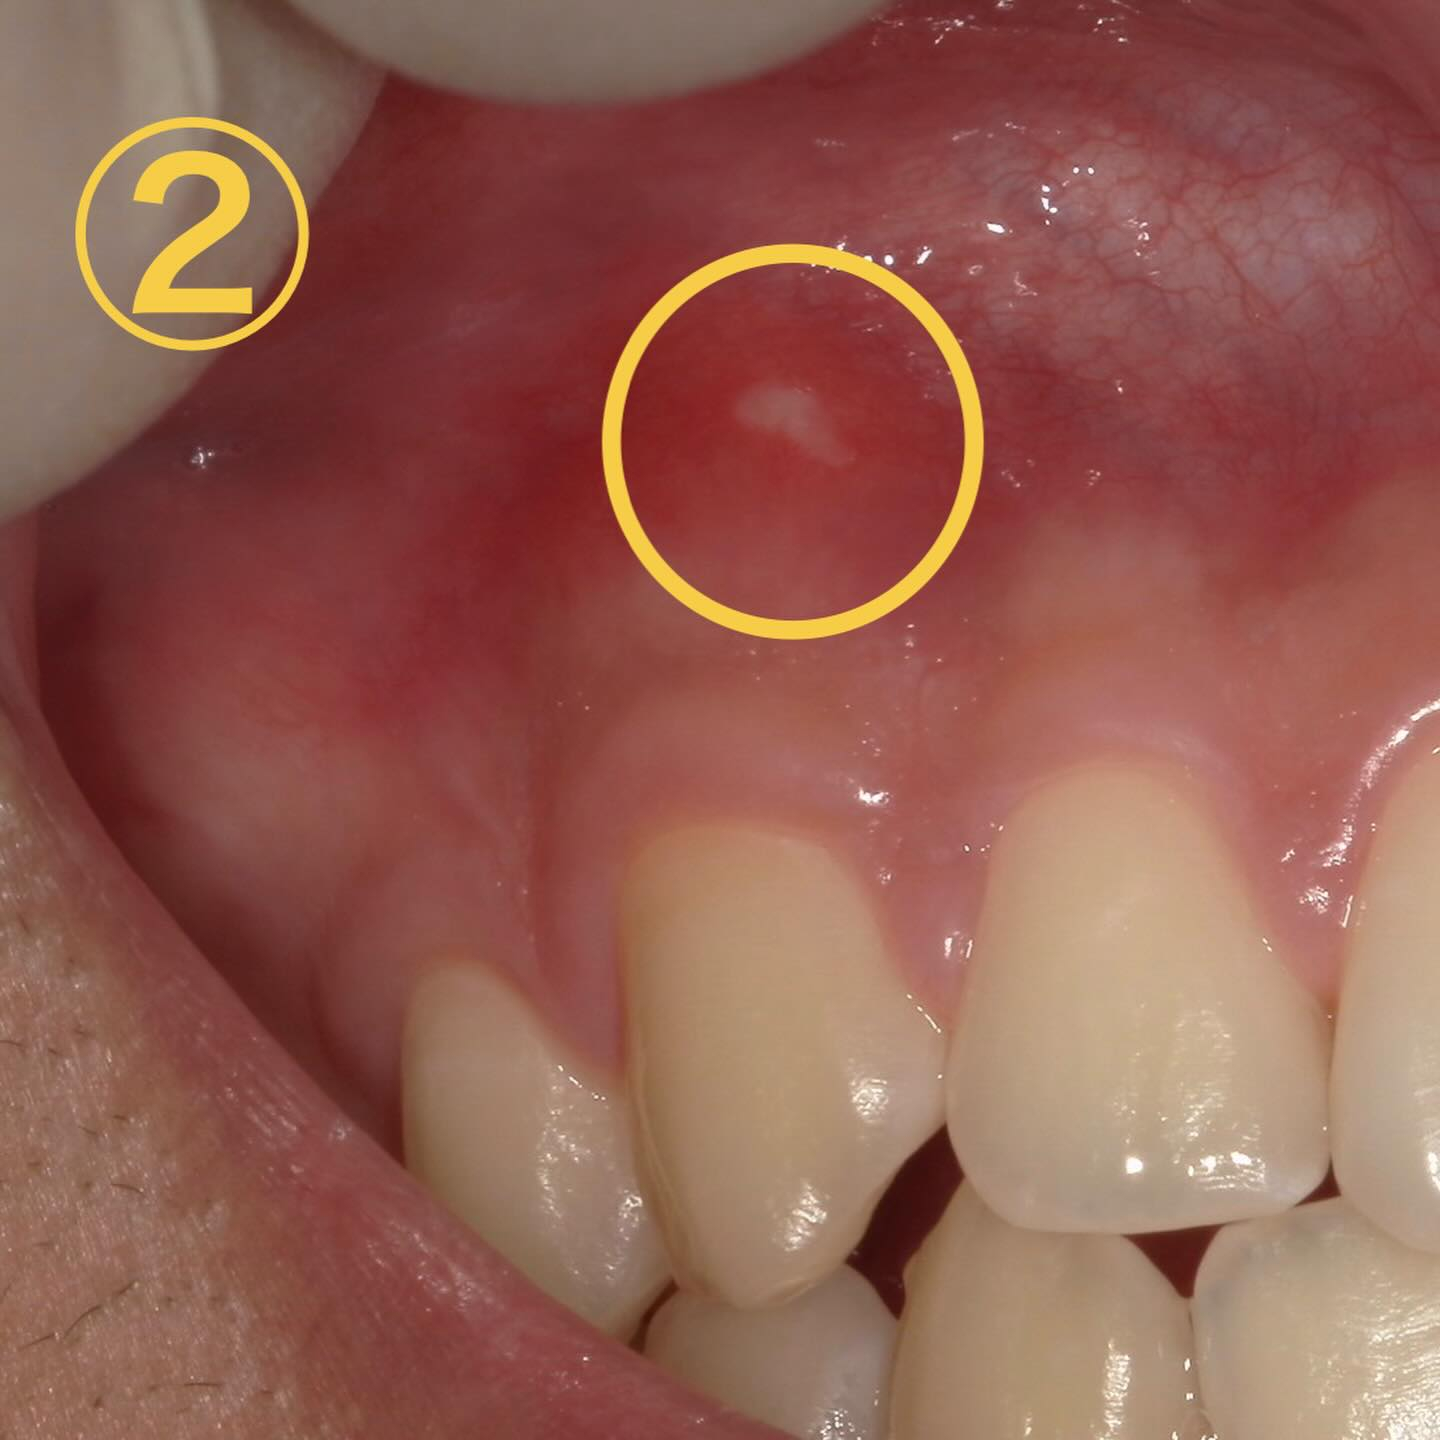

まず、画像①、②は典型的な口内炎です🧐

お二人とも歯磨き中に歯ブラシが滑って歯茎に当たったと仰ってました😱

特徴→・痛みがある・物が当たった等、原因となる心当たりがある・数日すると治って繰り返さない

💊治療法→塗り薬もあるのですが唾液で流れやすい為結局は経過観察がメインになります🥲